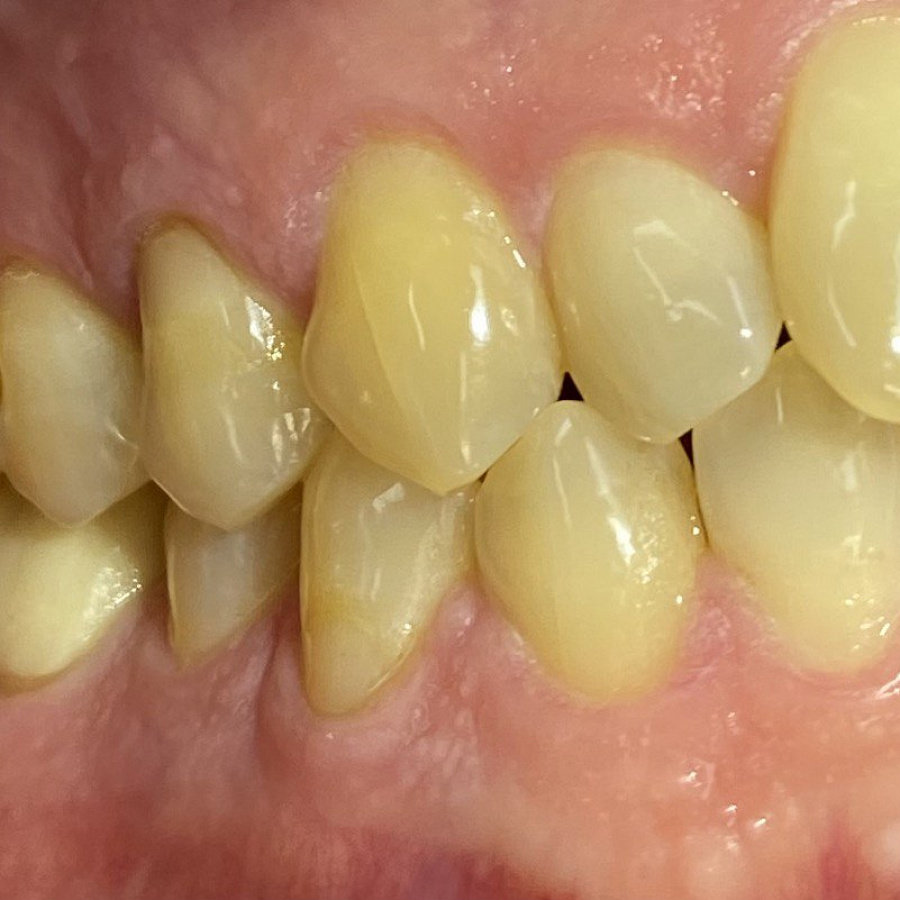

Пациент обратился с жалобами на неровные передние зубы верхней и нижней челюстей.

Диагностика показала:

• сужение зубных рядов,

• обратное перекрытие в области фронтальных зубов слева,

• разворот по оси передних зубов верхней и нижней челюстей,

• стираемость эмали зубов,

• индивидуальную микродентию 12 и 22 зубов.